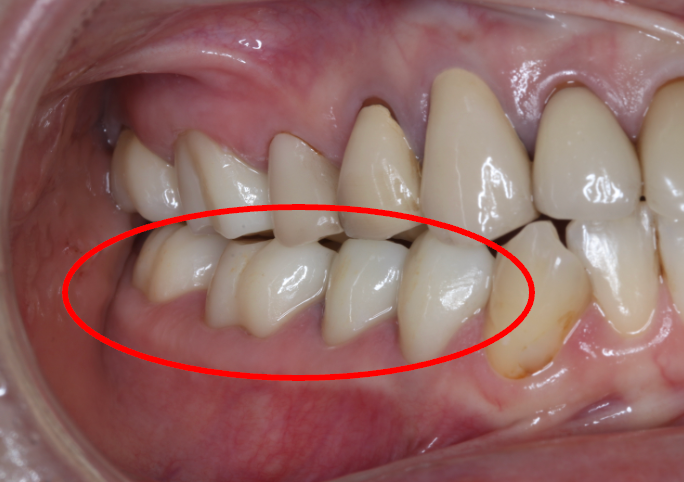

セラミック症例⑤

年齢50代女性

治療回数4回

治療内容セラミックインレー、クラウン

治療箇所

右下4番、5番、6番、7番 右上6番

治療費用500,000円